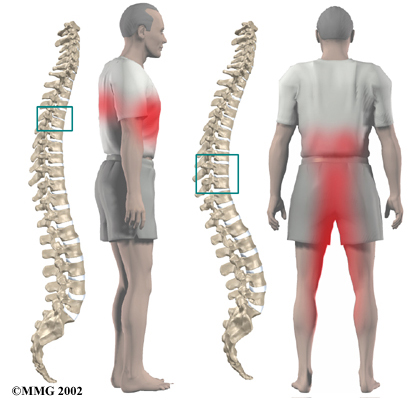

Symptoms of thoracic disc herniation vary widely. Symptoms depend on where and how big the disc herniation is, where it is pressing, and whether the spinal cord has been damaged.

Pain is usually the first symptom. The pain may be centered over the injured disc but may spread to one or both sides of the mid-back. Also, patients commonly feel a band of pain that goes around the front of the chest. Patients may eventually report sensations of pins, needles, and numbness. Others say their leg or arm muscles feel weak. Disc material that presses against the spinal cord can also cause changes in bowel and bladder function.

Disc herniations can affect areas away from the spine. Herniations in the upper part of the thoracic spine can radiate pain and other sensations into one or both arms. If the herniation occurs in the middle of the thoracic spine, pain can radiate to the abdominal or chest area, mimicking heart problems. A lower thoracic disc herniation can cause pain in the groin or lower limbs and can mimic kidney pain.